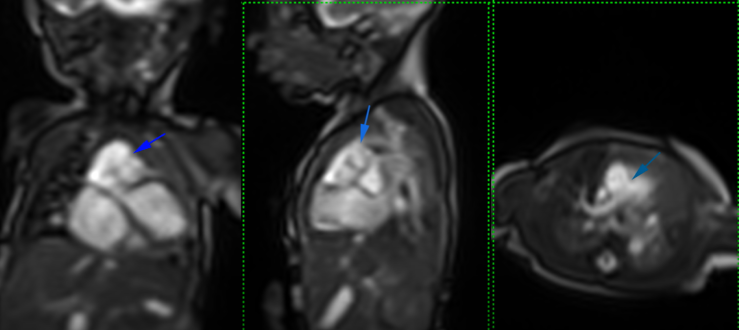

A full-term baby (male, birth weight 3.1 kg) was admitted with signs and symptoms of heart failure, but without cyanosis, at 10 days of life. His pulse oximeter indicated 96% on room air with respiratory rate 56/min, heart rate 147/min, blood pressure 69/35 mmHg. Chest X-ray showed plethoric lung fields and cardiomegaly (Fig. 1). Oxygen was given 1 L/min via a nasal cannula. Frusemide and spironolactone are started. His hemoglobin was 20.0 g/dL, hematocrit 58%, total white blood cells 13,600 µ/L, platelets 181,000 µ/L, CRP 0.1 mg/L, with normal renal function (urea 4.6 mmol/L, Na 133 mmol/L, K 4.5 mmol/L, Cl 95 mmol/L, Ca 2.35 mmol/L). An urgent 2D-Echo showed a large VSD, AP window (Fig. 2) and also PA sling suspected. Thoracic CT angiography confirmed Type 2a PA sling with severe tracheal stenosis. The so-called “tracheal bronchus” gave rise to the right upper lobe; its branching being as if at the usually expected location for the carina. The bifurcation to the right lower lobe and the left lung in this patient was present lower down with abnormal orientation (the bronchi more horizontally oriented than usual). The left PA is located at the T6–7 level just above the carina which resulted in distal airway stenosis (Fig. 3). The SVCs were bilateral structures. Lung volumes appeared fair bilaterally. The coronary arterial origins were normal. Cardiac MRI illustrated the right atrium and the right ventricle dilated, and also reconfirmed PA sling of the left PA as well as AP window between the distal AscAo and the right main PA (Supplementary Movie S1).

Journal of Pediatric Cardiology and Cardiac Surgery 7(1): 49-51 (2023)

Supplementary movie